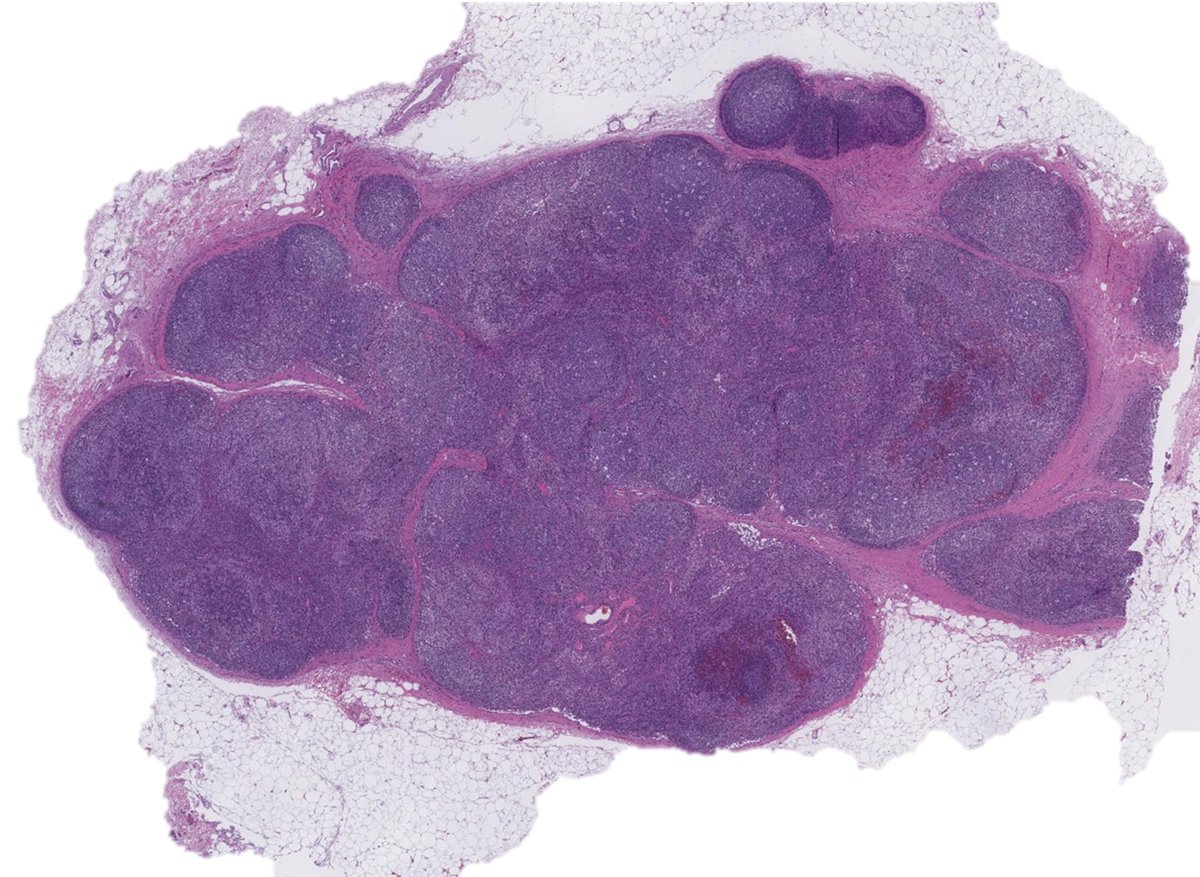

Special interest in #hemepath #breastpath #lymphoma #gynpath #pathology #Molpath